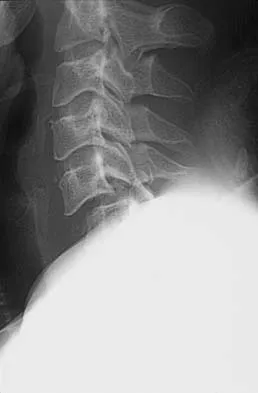

Figures 27a through 27c show the radiographs and CT scan of a 27-year-old man who sustained a low-velocity gunshot wound to the neck. He is quadriplegic (ASIA A), hemodynamically stable, and does not have drainage from his wound. After initial resuscitation and stabilization, the cervical spine and spinal cord injuries are best managed by

Explanation

Although the spinal canal has been penetrated, the lateral masses are intact bilaterally with only partial destruction of the vertebral body and penetration of the lamina on one side, thus the cervical spine is not unstable and surgical stabilization is not indicated. Dural repair is not indicated since there is no external cerebrospinal fluid leakage. Surgical treatment should be based on the need to treat extraspinal pathology only. Bono CM, Heary RF: Gunshot wounds to the spine. Spine J 2004;4:230-240.